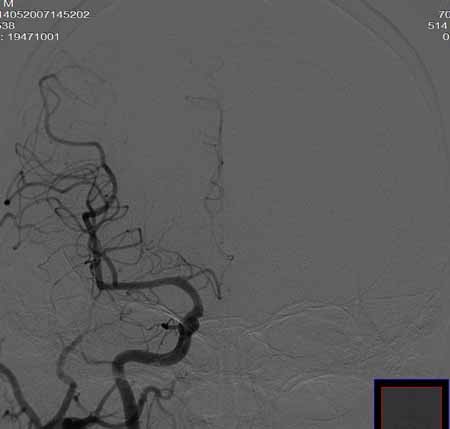

男,60岁。

腹主动脉、颈总动脉、颈内动脉狭窄支架置入术,最少放了三个支架吧,得十几万吧。

颈总动脉支架置入术。